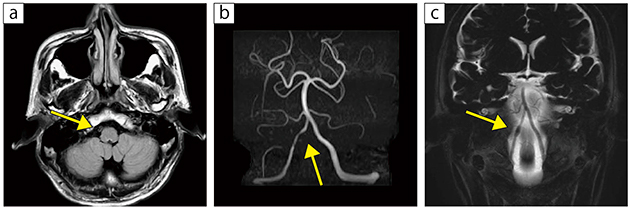

■症例3:未破裂椎骨動脈解離

40歳代,男性。2日前より出現した右項部から後頭部痛を主訴に同クリニック受診。FLAIR(a)で右椎骨動脈に壁在血栓様の高信号域を認め,MRA(b)で同部の内腔は狭窄し,3D-isoFSE(MPR像)(c)では同部の外腔が紡錘状に拡張している。

a:FLAIR,TR/TE=10000/117,FA=90°,スライス厚:5mm,撮像時間:3分41秒

b:3D-TOF,TR/TE=21.1/6.9,FA=20°,スライス厚:1.1mm,撮像時間:4分52秒

c:3D-isoFSE(COR),MPR(COR),TR/TE=3000/432,FA=90°,スライス厚:1.0mm,撮像時間:2分4秒,MPR処理:スライス厚8.0mm,スライス間隔1.0mm